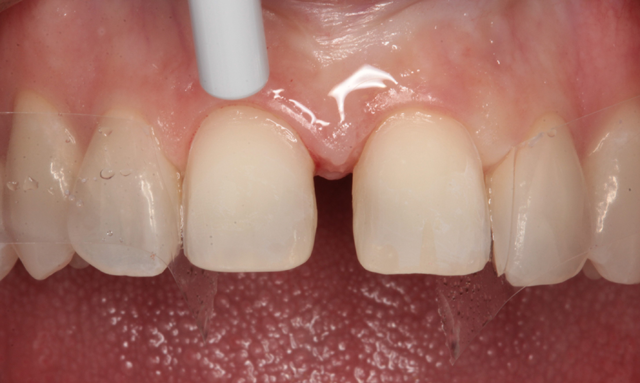

Celluloid strips were placed distal to both central incisors to protect the adjacent teeth. Phosphoric acid edging gel (Calibra, Dentsply/Sirona) was placed on the prepared enamel surfaces (Fig. 10), thoroughly rinsed after ten seconds (Fig. 11) and air dried (Fig. 12).

Fig. 11 Fig. 12